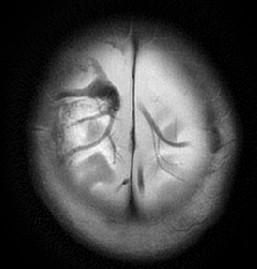

 Eye Findings 85% of AHT

 Hallmark of AHT:

 Macular Retinoschisis:  Acc-Dec vitreoretinal traction